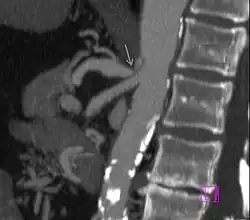

CT angiographic findings in MALS[2]

1. Focal narrowing of proximal celiac artery with poststenotic dilatation

2. Indentation on the superior aspect of the celiac artery

3. Hook-shaped contour of the celiac artery

Further evaluation and confirmation can be obtained via angiography to investigate the anatomy of the celiac artery.[5] Historically, conventional angiography was used, although this has been largely replaced by less invasive techniques such as computed tomography (CT) and magnetic resonance (MR) angiography.[2][5] Because it provides better visualization of intra-abdominal structures, CT angiography is preferred to MR angiography in this setting.[5] The findings of focal narrowing of the proximal celiac artery with poststenotic dilatation, indentation on the superior aspect of the celiac artery, and a hook-shaped contour of the celiac artery support a diagnosis of MALS.[2] These imaging features are exaggerated on expiration, even in normal asymptomatic individuals without the syndrome.[2]

Proximal celiac artery stenosis with poststenotic dilatation can be seen in other conditions affecting the celiac artery.[2] The hook-shaped contour of the celiac artery is characteristic of the anatomy in MALS and helps distinguish it from other causes of celiac artery stenosis such as atherosclerosis.[2] This hooked contour is not entirely specific for MALS however, given that 10–24% of normal asymptomatic individuals have this anatomy.[2]